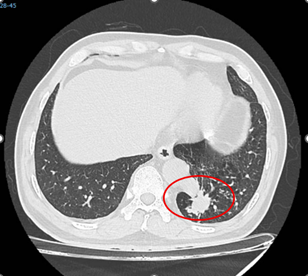

Trường hợp ông N.N.T (56 tuổi, Tây Ninh) là một tình huống hiếm gặp. Ông tình cờ phát hiện tổn thương thùy dưới phổi trái khi đi khám tổng quát. Tại Bệnh viện Bình Dân, các bác sĩ chẩn đoán ông mắc phổi biệt lập nội thùy với khối kích thước 23 mm × 26 mm. Đáng chú ý, động mạch nuôi khối này xuất phát trực tiếp từ động mạch chủ xuống với đường kính lên tới 17 mm – một kích thước rất lớn và đầy rủi ro nếu người bệnh không được điều trị.

Nếu một người có các triệu chứng như viêm phổi tái diễn tại một vị trí, ho ra máu hoặc tình cờ phát hiện khối bất thường ở phổi, hãy đến các cơ sở y tế chuyên sâu để được tầm soát. Chẩn đoán hình ảnh như MSCT có thể phát hiện phần phổi biệt lập.